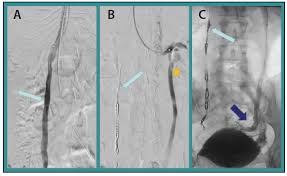

Small volumes (20cc max) of sotradecol sclerosant admixed with air are injected under fluoroscopy to ablate the epithelial cyst lining. 1% 20 mg/2 ml (10 mg/ml): Many agents have been used to occlude the isv. Has been administered as an endovenous foam or microfoam; 2ml of.25% was used for the procedure. Sotradecol foam was injected into each site under fluoroscopic guidance using negative contrast/contrast displacement technique (fig. It is visible via ultrasound and can be easily tracked and guided to the source of the problematic vein. However, when talking about doing sclerotherapy involving the legs, sotradecol is the more commonly accepted drug of choice. Is the best of the foam sclerosants. It is easy to use, has few side effects and gives excellent results. Asclera and sotradecol are both fda approved sclerosants and both have a very safe record for many years (even prior to fda approval in the generic form). There are a multitude of sclerosants out there, not all of which are appropriate for the legs. It is sold for medical use as a solution of up to 3% concentration with 2% benzoyl alcohol used as a stabilant.